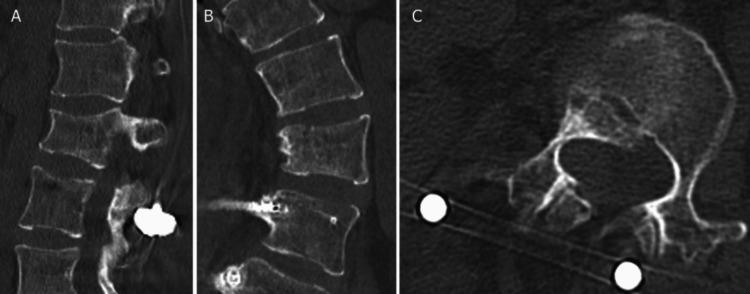

Lumbar spine instability fractures in patients with residual adolescent idiopathic scoliosis (AIS) are rare, and optimal treatment strategies remain unclear. Surgical management must consider both immediate fracture stabilization and the potential need for future scoliosis correction. A 24-year-old woman with residual AIS (Cobb angles: 47° thoracic, 60° lumbar) sustained an AO Spine Classification Type B2 lumbar fracture (L2) after falling from the second floor. She presented with severe back pain but no neurological deficits. Radiographic evaluation confirmed vertebral body collapse and posterior ligamentous injury. Posterior fixation alone was chosen over combined anterior-posterior fixation to maintain future options for scoliosis correction. The patient recovered uneventfully, achieving solid bone fusion by seven months postoperatively, at which time the implants were also removed. At the two-year follow-up, she remained asymptomatic with no progression of scoliosis or instability. For lumbar fractures in patients with residual AIS, surgical decision-making should consider future scoliosis management. Posterior fixation alone may be a viable strategy to ensure both stability and surgical flexibility.

残留青少年特发性脊柱侧凸(AIS)患者的腰椎不稳定骨折较为罕见,最佳治疗策略仍不明确。手术治疗必须兼顾即刻的骨折稳定以及未来脊柱侧凸矫正的潜在需求。一名24岁残留AIS(Cobb角:胸椎47°,腰椎60°)的女性从二楼坠落,发生AO脊柱分类B2型腰椎骨折(L2)。她表现为严重背痛,但无神经功能缺损。影像学评估证实椎体塌陷和后韧带损伤。选择单纯后路固定而非前后联合固定,以保留未来脊柱侧凸矫正的选择。患者恢复顺利,术后7个月实现了牢固的骨融合,此时植入物也被取出。在两年随访时,她无症状,脊柱侧凸或不稳定均无进展。对于残留AIS患者的腰椎骨折,手术决策应考虑未来的脊柱侧凸治疗。单纯后路固定可能是确保稳定性和手术灵活性的可行策略。